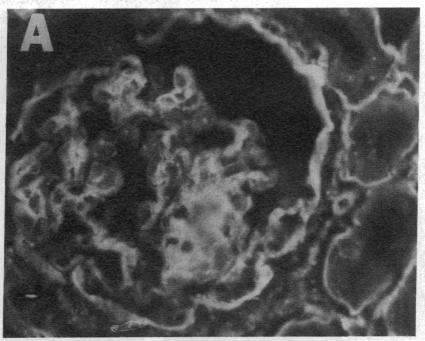

The pathogenesis of renal fibrosis in crescentic nephritis is incompletely understood. To improve our understanding of this process, crescentic nephritis was induced in New Zealand White rabbits by administration of guinea pig antiglomerular basement membrane IgG after sensitization with guinea pig IgG, and their kidneys were analyzed for the development of fibrosis. Collagen synthesis in renal cortical tissue was significantly elevated by day 3, peaked at days 7-15, and returned towards baseline by day 21. Collagen content of both glomeruli and cortex were increased starting on days 14-16, and remained constant in cortex thereafter. Light microscopic analysis was much less sensitive, revealing fibrosis only after day 21. Immunofluorescence revealed that type IV collagen was distributed primarily in the glomerulus, while types I and III were increased in the glomerulus and interstitium. Thus, in this model of crescentic nephritis, fibrosis, as assessed biochemically, developed early at time points when morphologic analysis failed to detect such a development. Hence early therapeutic intervention, before morphologic evidence of fibrosis is evident, may be more successful in arresting the progression of this disease before it reaches irreversible terminal stages.

新月体性肾炎肾纤维化的发病机制尚未完全明确。为增进对这一过程的了解,在用豚鼠免疫球蛋白G致敏后,给新西兰白兔注射豚鼠抗肾小球基底膜免疫球蛋白G以诱发新月体性肾炎,并对其肾脏进行纤维化发展情况分析。肾皮质组织中的胶原蛋白合成在第3天显著升高,在第7 - 15天达到峰值,并在第21天恢复至基线水平。肾小球和皮质的胶原蛋白含量从第14 - 16天开始增加,此后皮质中的含量保持稳定。光学显微镜分析的敏感性要低得多,仅在第21天后才显示出纤维化。免疫荧光显示,IV型胶原蛋白主要分布在肾小球中,而I型和III型在肾小球和间质中增加。因此,在这个新月体性肾炎模型中,通过生化评估发现,纤维化在形态学分析未能检测到这种发展的早期时间点就已出现。因此,在纤维化的形态学证据明显之前进行早期治疗干预,可能更成功地在疾病发展到不可逆的终末期之前阻止其进展。